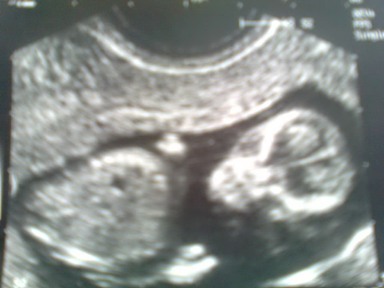

Örülök, hogy a hangulatingadozásokkal nem vagyok egyedül! De a súlyomtól egy kicsit megijedtem! Úgy tűnik, én vezetek a +3 kg-val...